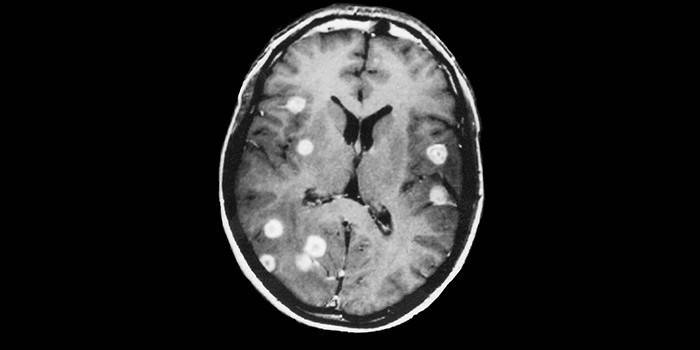

Com a disseminação de neoplasias no câncer de mama e pulmão, elas afetam o cérebro e são transferidas com o líquido linfático e o sangue. Então eles param em uma determinada área, saem do vaso e formam um foco de metástase. Esse processo se desenvolve lentamente no estágio inicial, muitas vezes ocorre de forma assintomática, portanto, os médicos não conseguem notá-los imediatamente.

- Se metástases entram no cérebro, uma pessoa desenvolve desorientação, dor de cabeça, náusea, tontura, problemas de fala e visão e dificuldade para andar.

- Solitário. Este tipo é manifestado na forma de formações únicas de grandes nós que estão localizadas no cérebro, tecido pulmonar.

A escolha de um teste adequado é determinada pela localização do tumor primário. Um oncologista pode diagnosticar tumores metastáticos usando métodos de imagem (geralmente tomografia computadorizada). É possível fazer isso apenas quando eles atingem uma massa aparente, a doença é muitas vezes extremamente difícil de tratar nesta fase. O diagnóstico precoce do câncer metastático aumenta significativamente a chance de sobrevivência do paciente. Use os seguintes casos de teste:

- RM (ressonância magnética);